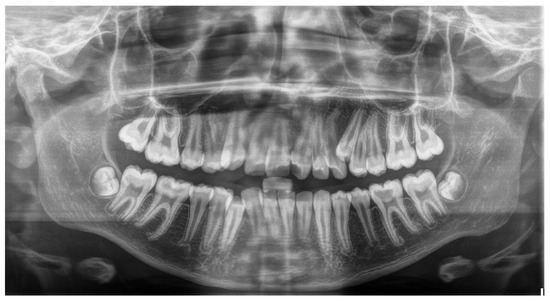

Figure 1. Panoramic radiograph of a patient with supernumerary mandibular left right premolar.

Figure 2. Panoramic radiograph of a patient with supernumerary maxillary left premolar.